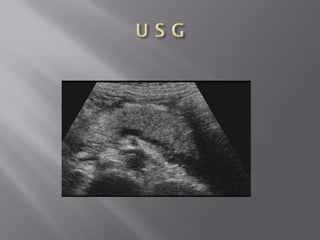

• 39.

 Cholecystitis  Occurswhen a calculus obstructs the cystic duct. The trapped bile causes inflammation of the gallbladder wall.  U S G is the preferred imaging method for the evaluation of cholecystitis, also allowing assessment of the compressibility of the gallbladder.  The diagnosis of a hydropic gallbladder is solely made on the non-compressability of the gallbladder.